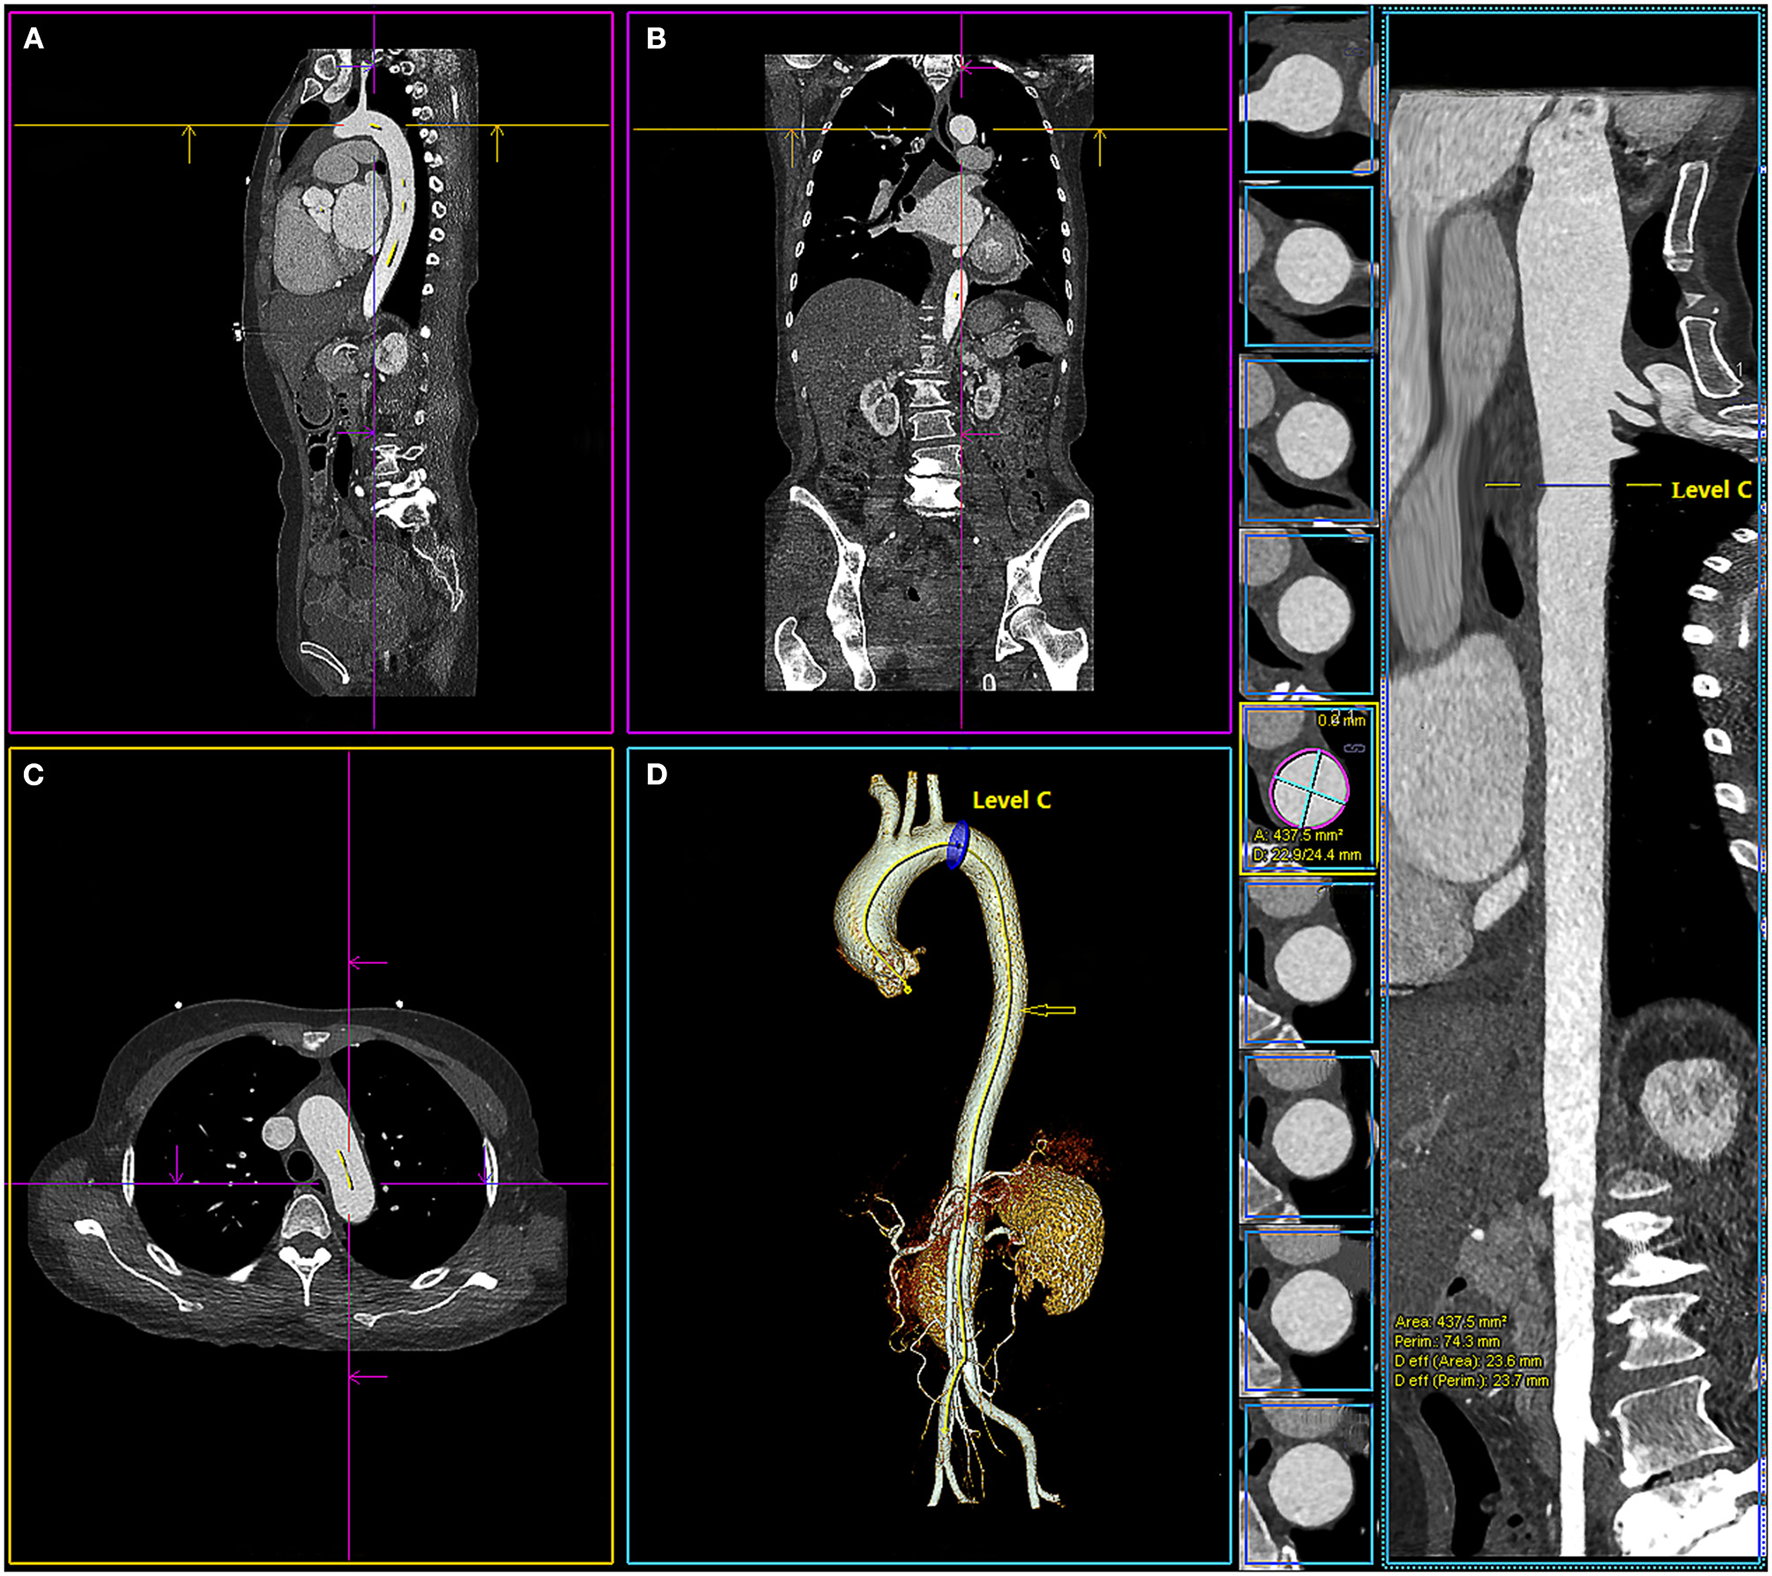

Three segmentations within the aortic arch and proximal descending aorta (level A, 1 cm proximal to the innominate artery; level B, 1 cm distal to the left common carotid artery; and level C, 1 cm distal to the left subclavian artery) were selected, as these were the typical proximal sealing zone for stent-grafts of the thoracic aorta and aortic arch (16) (Figure 2). The morphometric parameter measurements included the maximum aortic diameter, the minimum aortic diameter, the lumen area, the lumen perimeter, and the diameter derived from the lumen area. The measurements were made in a multi-planar view perpendicular to the semi-automatically created centerline. The centerline was adjusted manually in cases where it was not created accurately by the software [when adjusting the centerline manually, the identified centerline should be observed on multi-planar views (axial, coronal, and sagittal) and the cardiopulmonary resuscitation (CPR) image to make sure the centerline was centered in the blood vessel]. If the automatically detected contour of the aorta was incorrect, then it will be manually modified. The system could measure the maximum aortic diameter and minimum aortic diameter on the axial image perpendicular to the centerline and calculated the area, perimeter, and diameter derived from the lumen area automatically (Figure 3; Supplementary Figure S1).

Figure 3

Multiplanar views of aortic measurements in sagittal view (A), frontal (B), axial (C), 3-dimensional (D), and the centerline of the aorta (

) with the location of level C (1 cm distal to the left subclavian artery). The system calculated the maximum and minimum aortic diameter (D: 22.9/24.4 mm), area (area: 437.5 mm2), perimeter (perim: 74.3 mm), and diameter derived from the lumen area [Deff (area): 23.6 mm] automatically.